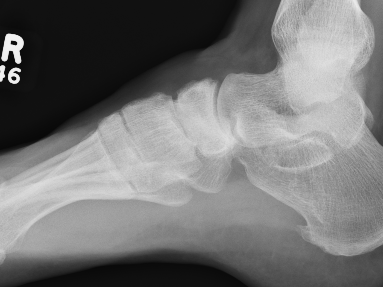

Xray

Sclerosis / Fragmentation

Talonavicular osteoarthritis

Talocuneiform osteoarthritis

Midfoot collapse